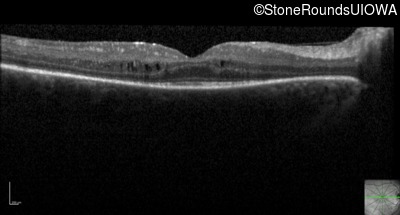

Optical Coherence Tomography - Left - 20/50 -3

Exemplar / OCT Stack